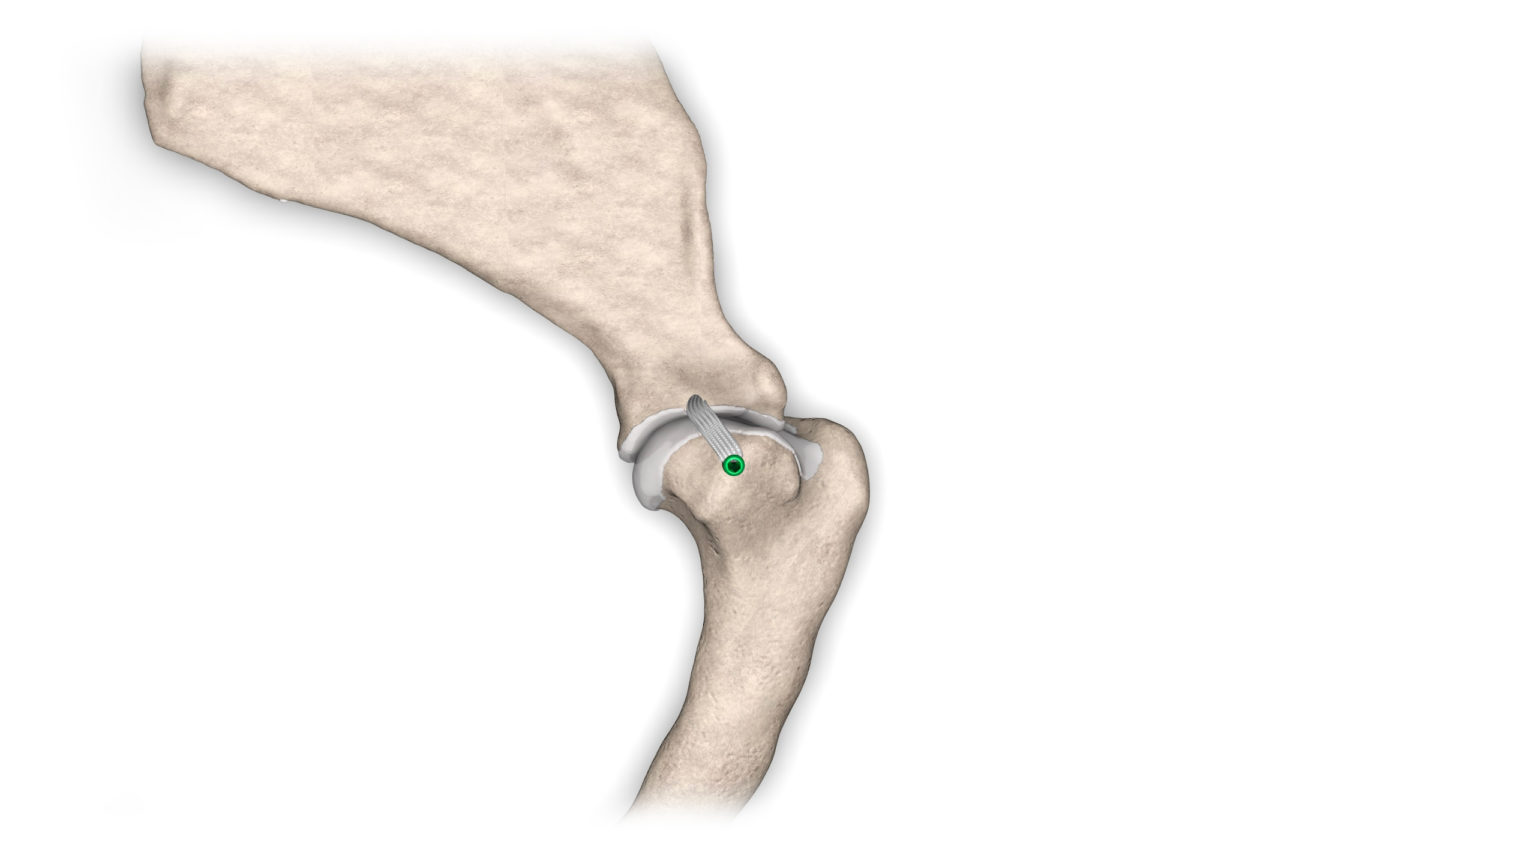

V případě ruptury kraniálního zkříženého vazu umožňuje ExtraTape® extraartikulární rekonstrukci co nejblíže izometrii původního vazu, čímž rychle a trvale stabilizuje koleno bez uzlů a zvlnění, což je slabina tradičnějších technik extraartikulární stabilizace. Ty jsou zde nahrazeny pevným ukotvením kosti pomocí interferenčního šroubu.

Řešení, které respektuje původní anatomii, obnovuje funkci postiženého vazu a je dostupné v rámci otevřené nebo artroskopické chirurgie.